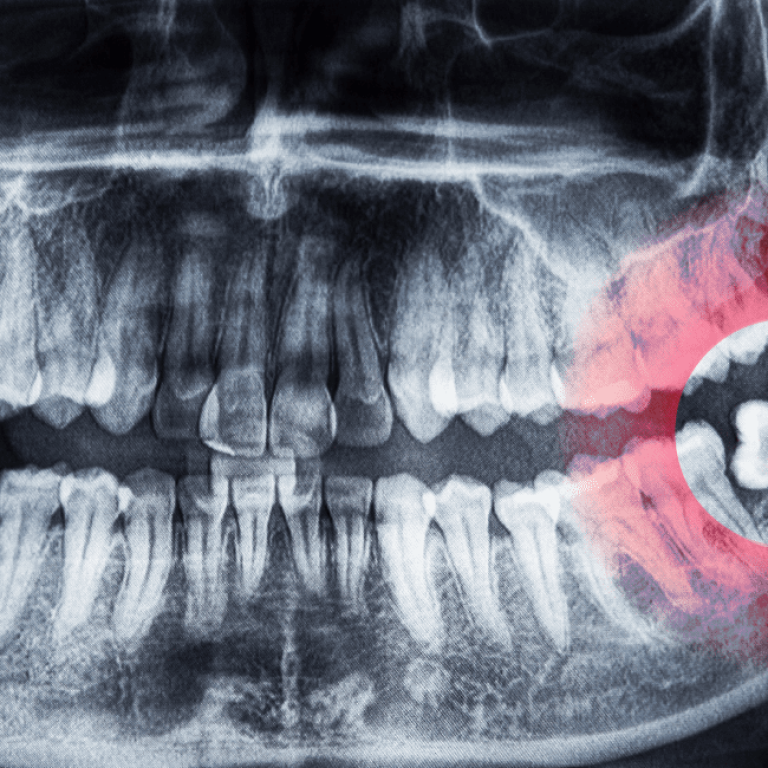

Gentle and precise removal of troublesome wisdom teeth, providing relief from pain and preventing potential oral complications.